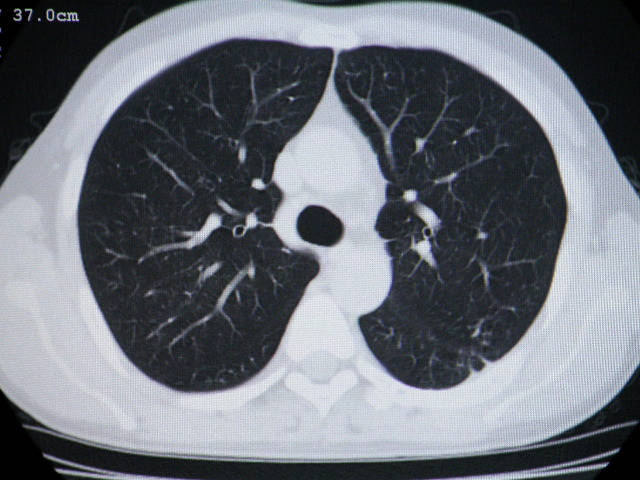

肺内结节在纵隔窗内测ct值为43hu

左肺下叶背段软组织结节,偏心空洞,周围见长纤维所条及卫星灶,首先考虑结核球,周围型肺癌待排。

左肺下叶偏心软组织肿块,边缘毛刺征,胸膜凹陷征

左肺下叶偏心软组织肿块,边缘毛刺征,胸膜凹陷征,血管集束症